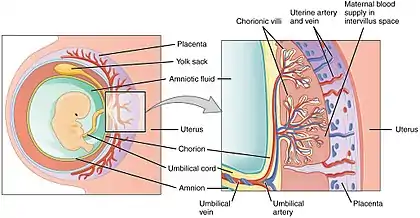

Placental mammals, including humans, have a chorioallantoic placenta that forms from the chorion and allantois. In humans, the placenta averages 22 cm (9 inch) in length and 2–2.5 cm (0.8–1 inch) in thickness, with the center being the thickest, and the edges being the thinnest. It typically weighs approximately 500 grams (just over 1 lb). It has a dark reddish-blue or crimson color. It connects to the fetus by an umbilical cord of approximately 55–60 cm (22–24 inch) in length, which contains two umbilical arteries and one umbilical vein.[12] The umbilical cord inserts into the chorionic plate (has an eccentric attachment). Vessels branch out over the surface of the placenta and further divide to form a network covered by a thin layer of cells. This results in the formation of villous tree structures. On the maternal side, these villous tree structures are grouped into lobules called cotyledons. In humans, the placenta usually has a disc shape, but size varies vastly between different mammalian species.[13]

In preparation for implantation of the blastocyst, the endometrium undergoes decidualization. Spiral arteries in the decidua are remodeled so that they become less convoluted and their diameter is increased. The increased diameter and straighter flow path both act to increase maternal blood flow to the placenta. There is relatively high pressure as the maternal blood fills intervillous space through these spiral arteries which bathe the fetal villi in blood, allowing an exchange of gases to take place. In humans and other hemochorial placentals, the maternal blood comes into direct contact with the fetal chorion, though no fluid is exchanged. As the pressure decreases between pulses, the deoxygenated blood flows back through the endometrial veins.

Fetoplacental circulation

Deoxygenated fetal blood passes through umbilical arteries to the placenta. At the junction of umbilical cord and placenta, the umbilical arteries branch radially to form chorionic arteries. Chorionic arteries, in turn, branch into cotyledon arteries. In the villi, these vessels eventually branch to form an extensive arterio-capillary-venous system, bringing the fetal blood extremely close to the maternal blood; but no intermingling of fetal and maternal blood occurs ("placental barrier").[20]

A 3D Power Doppler image of vasculature in 20-week placenta Schematic view of the placenta

Schematic view of the placenta Maternal side of a whole human placenta, just after birth